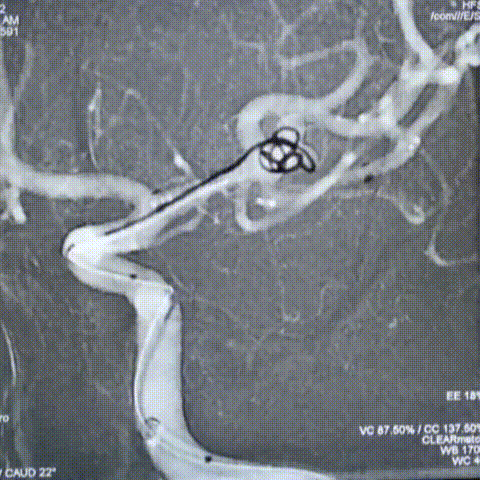

栓塞过程

先通过微导管填塞成篮圈,输送支架到左侧大脑中动脉下干并释放,使支架覆盖动脉瘤开口。依次填入Jasper®SS弹簧圈多枚。

术后即刻影像